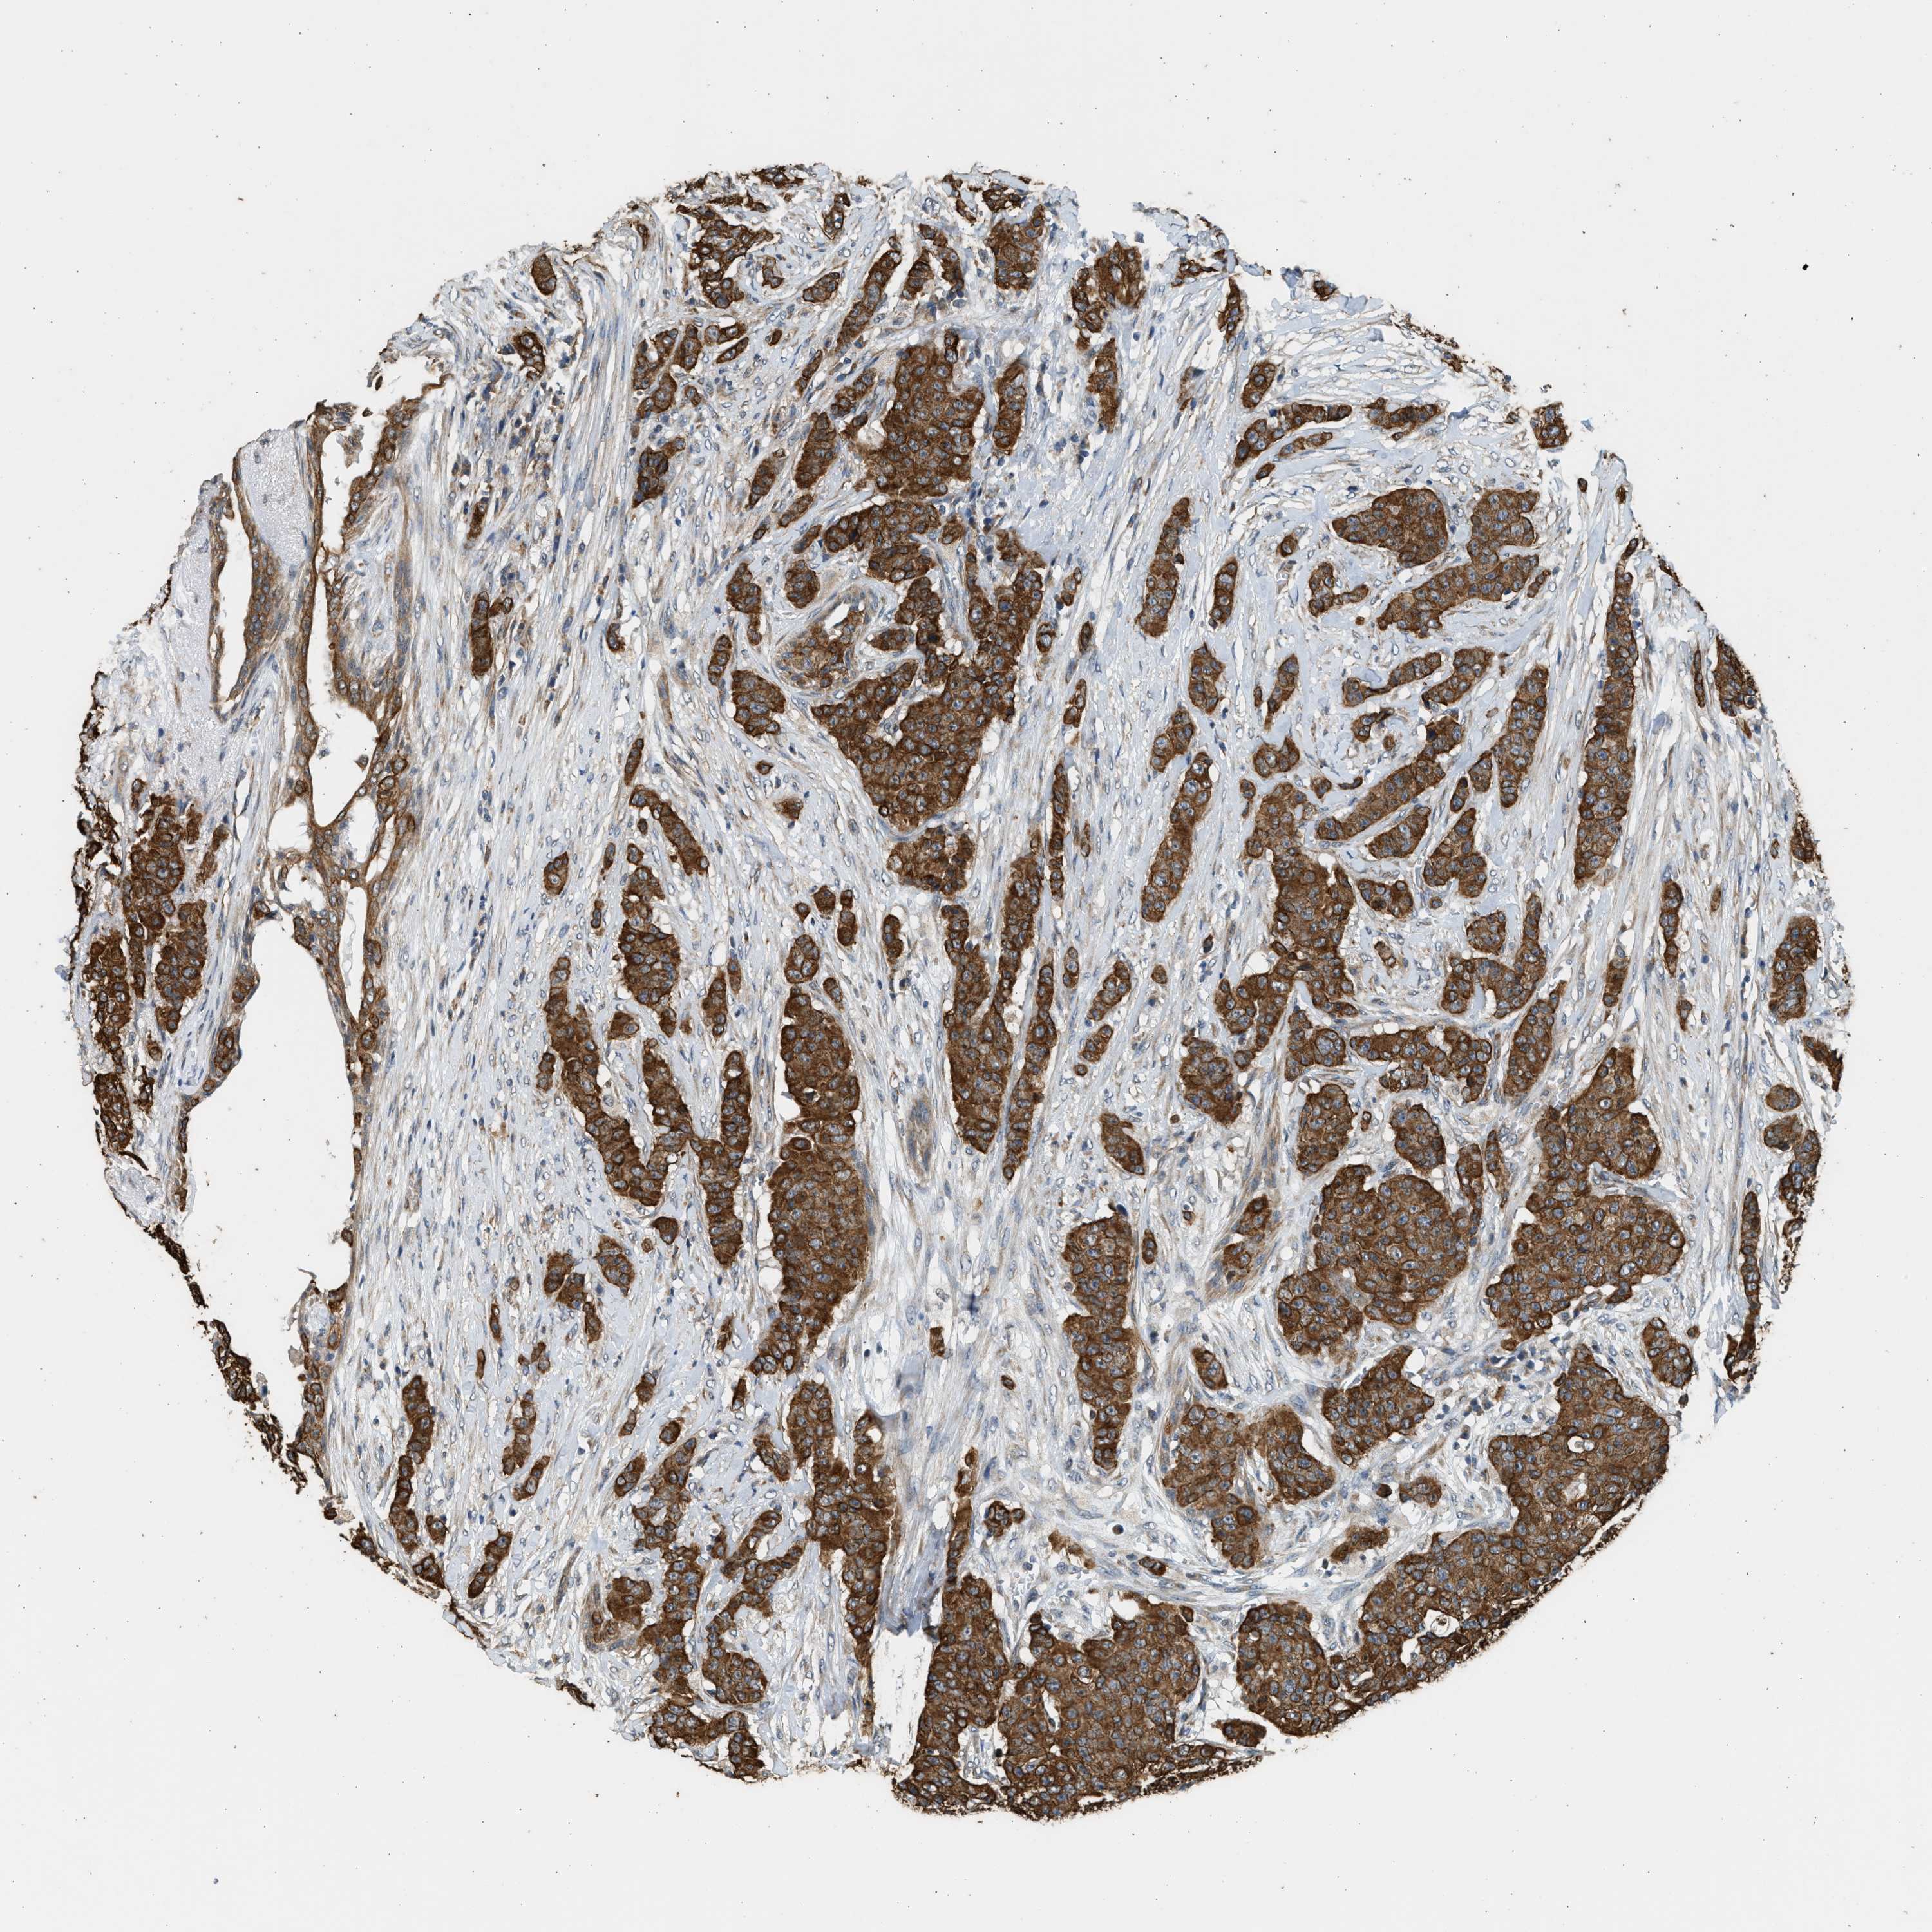

CANCER BREAST CANCER Show tissue menu

BRCA TCGA BRCA VALIDATION PROTEIN EXPRESSION